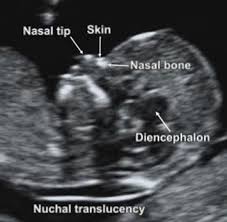

2. Αυχενική Διαφάνεια. 11  –  13+6  Εβδομάδες

A. Ελέγχονται οι πιθανότητες του συνδρόμου Down και άλλων χρωμοσωμικών ανωμαλιών.

Παρέχεται η δυνατότητα του υπολογισμού του ατομικού κινδύνου για κάθε γυναίκα σχετικά με την παρούσα κύηση. Για τον καθορισμό του κινδύνου συνυπολογίζονται:

• Η ηλικία της μητέρας

• Τα επίπεδα δυο ορμονών στο αίμα της (PAPP-A , b HCG )

• Το πάχος της αυχενικής διαφάνειας του εμβρύου (NT)

• Η παρουσία του ρινικού οστού

• Η διαφυγή του αίματος στην τριγλώχινα βαλβίδα της καρδιάς

• Η ροή του αίματος στο φλεβώδη πόρο του εμβρύου (εμβρυική κυκλοφορία)

• Η μέτρηση της μετωποζυγωματικής γωνίας